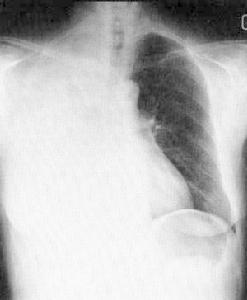

3.肝腎陰虛面色晦暗,午後兩顴發赤,目眶黯黑,皮膚乾燥色枯,發枯不澤或脫髮,形體明顯消瘦,精神萎靡不振,間或煩躁易怒,夜間潮熱盜汗,失眠多夢,頭暈目花,軟弱無力。舌質暗紅或絳,舌苔薄少,脈沉細弦澀。本型常系腎上腺結核患者的臨床表現,在腎上腺區x線平片上常可發現鈣化陰影,可作為本病系結核性的有力佐證。